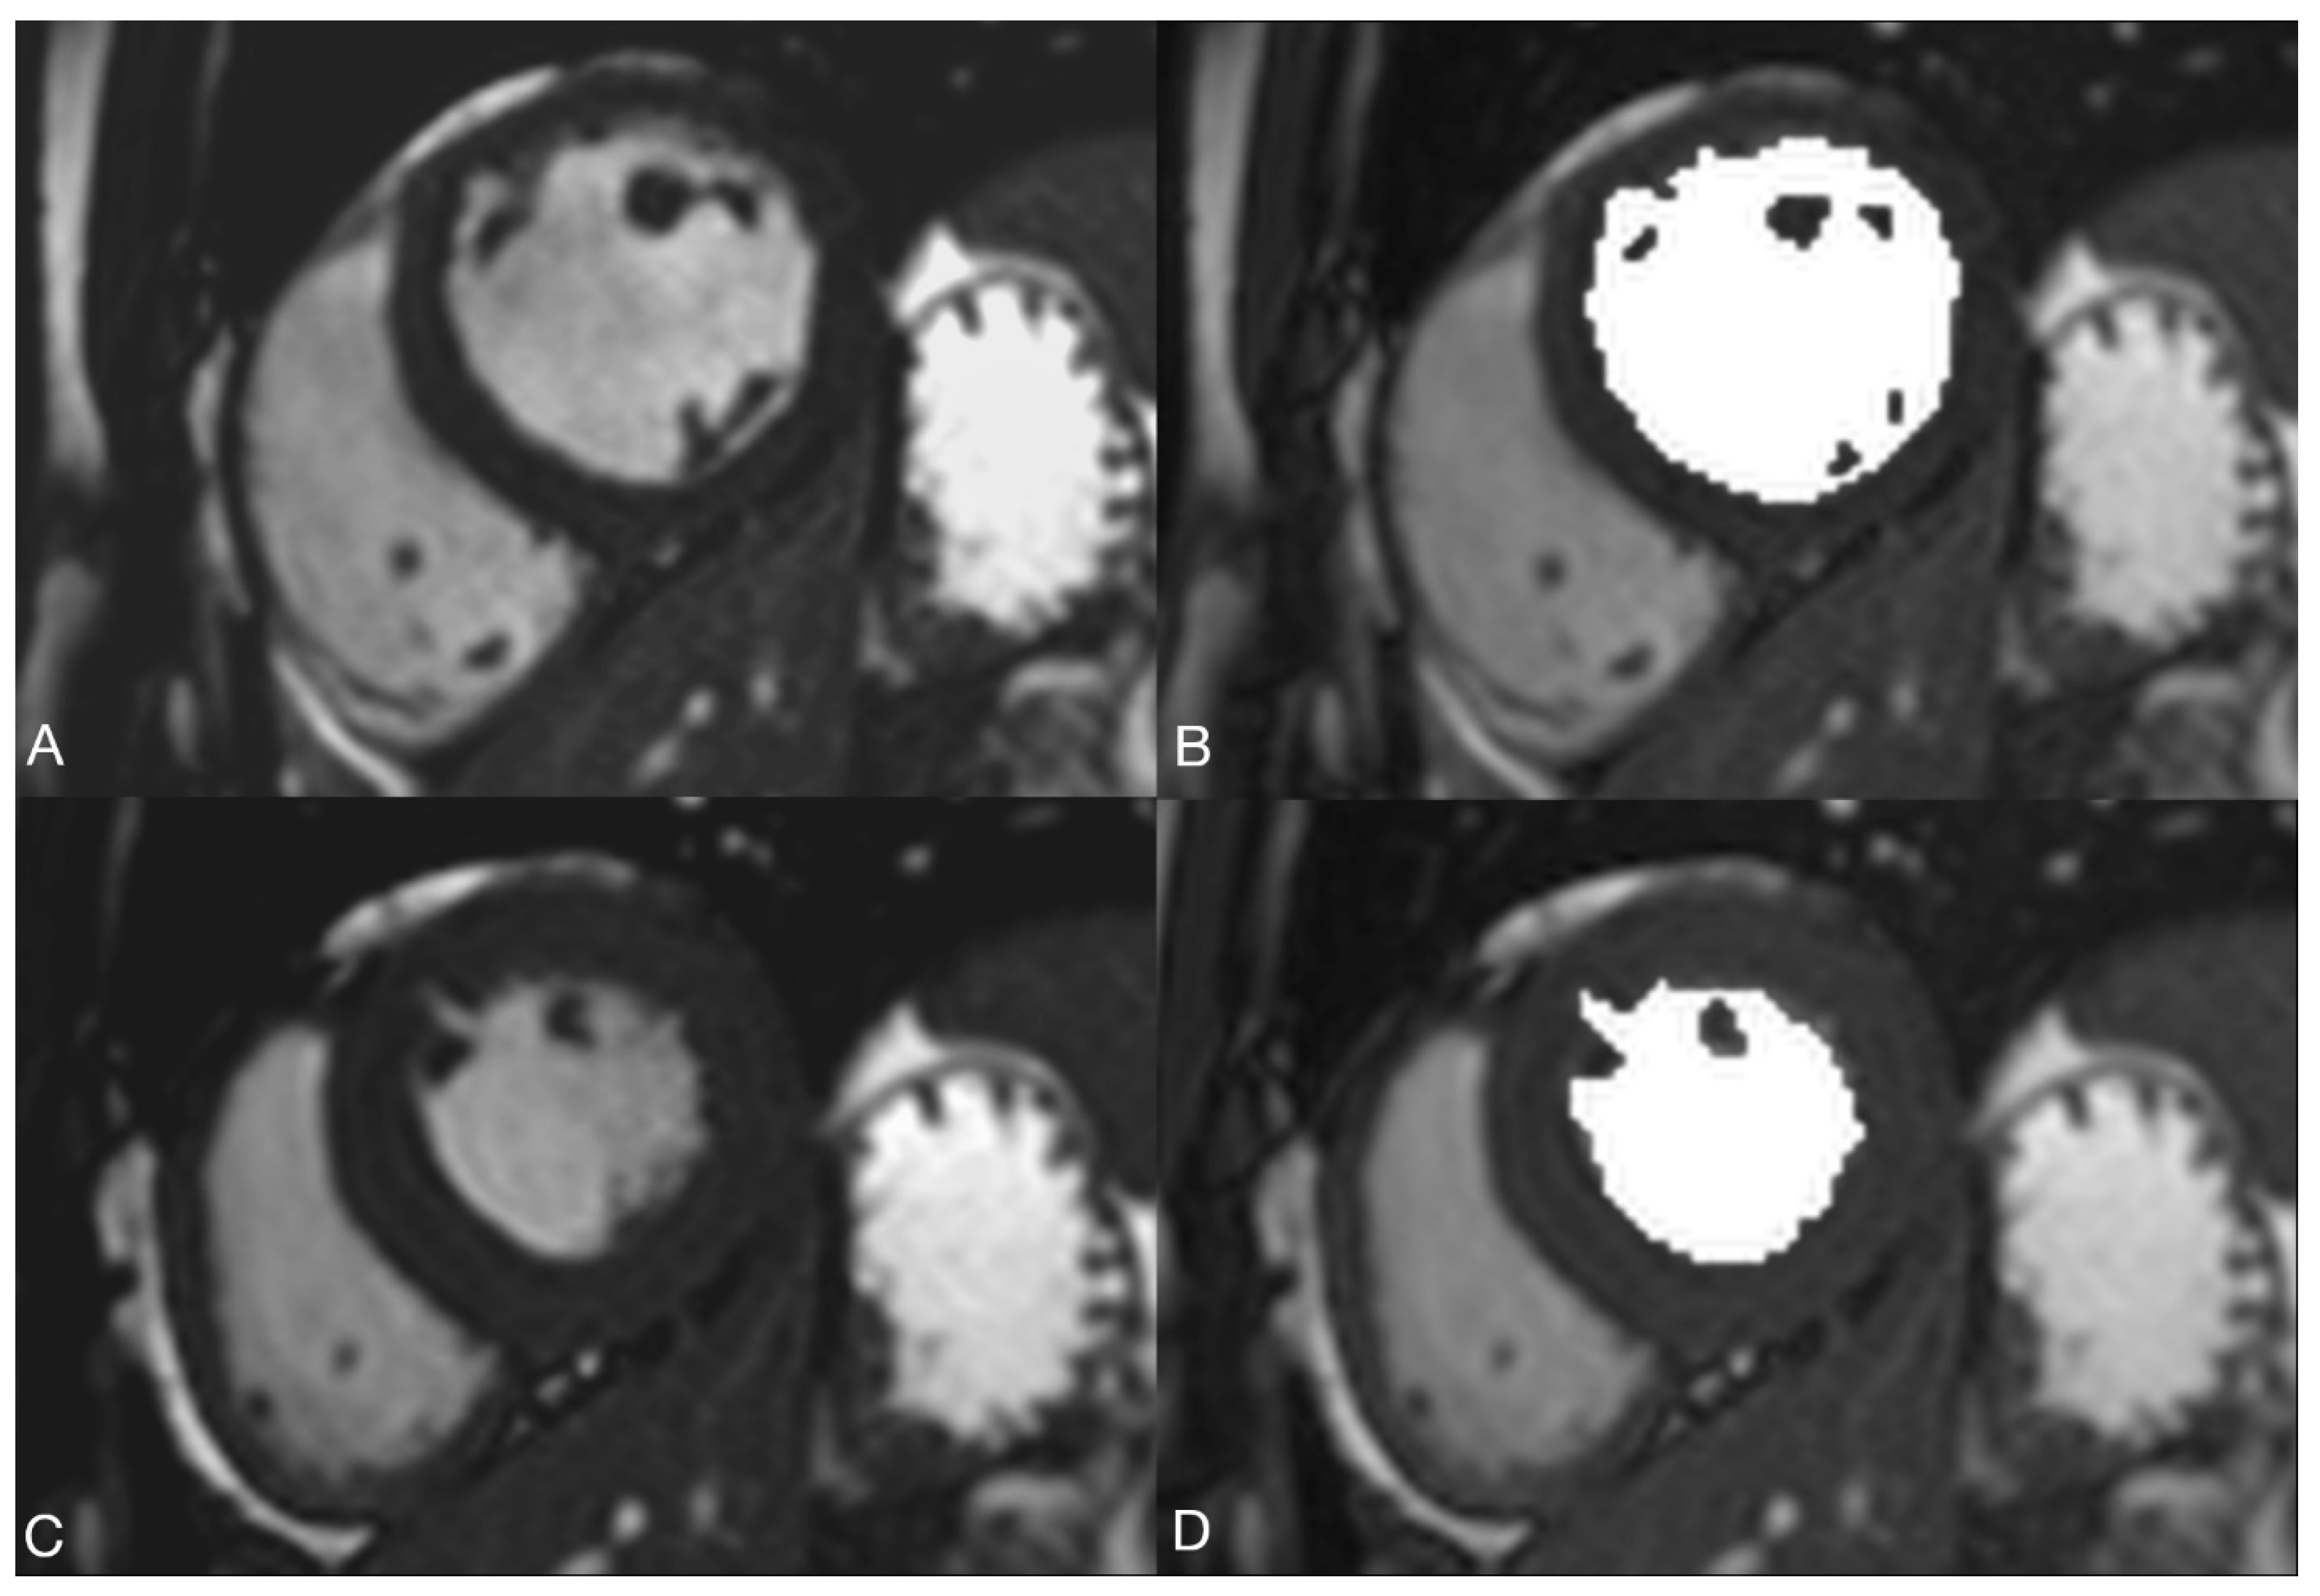

2.2.2. Volume Determination with the Pixel-Based Method (PbM)

2.2.3. Volume Determination According to the Contour Surface Method (=KfM) with SyngoVia

2.2.4. Volume Determination according to the Contour Area Method (=KfM) with cvi42